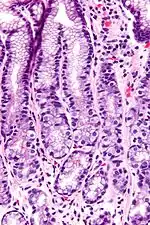

G cells have a distinctive microscopic appearance that allows one to separate them from other cells in the gastric antrum; their nuclei are centrally located in the cell. They are found in the middle portion of the gastric glands.